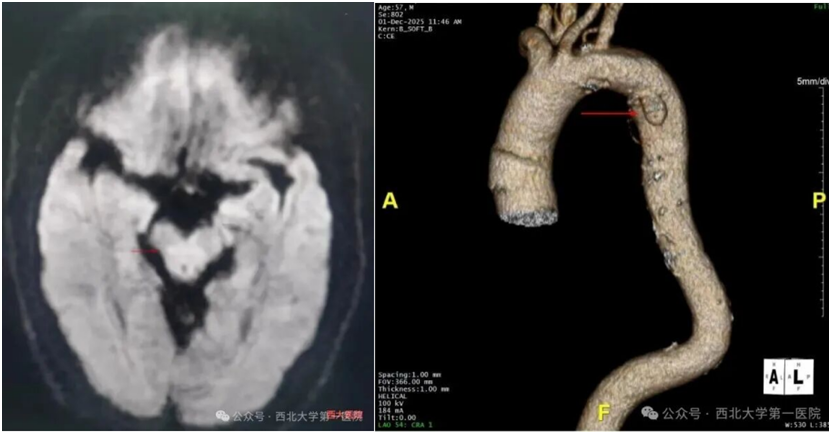

中老年人头晕、口齿不清?西北大学第一医院介入手术快速“清障”